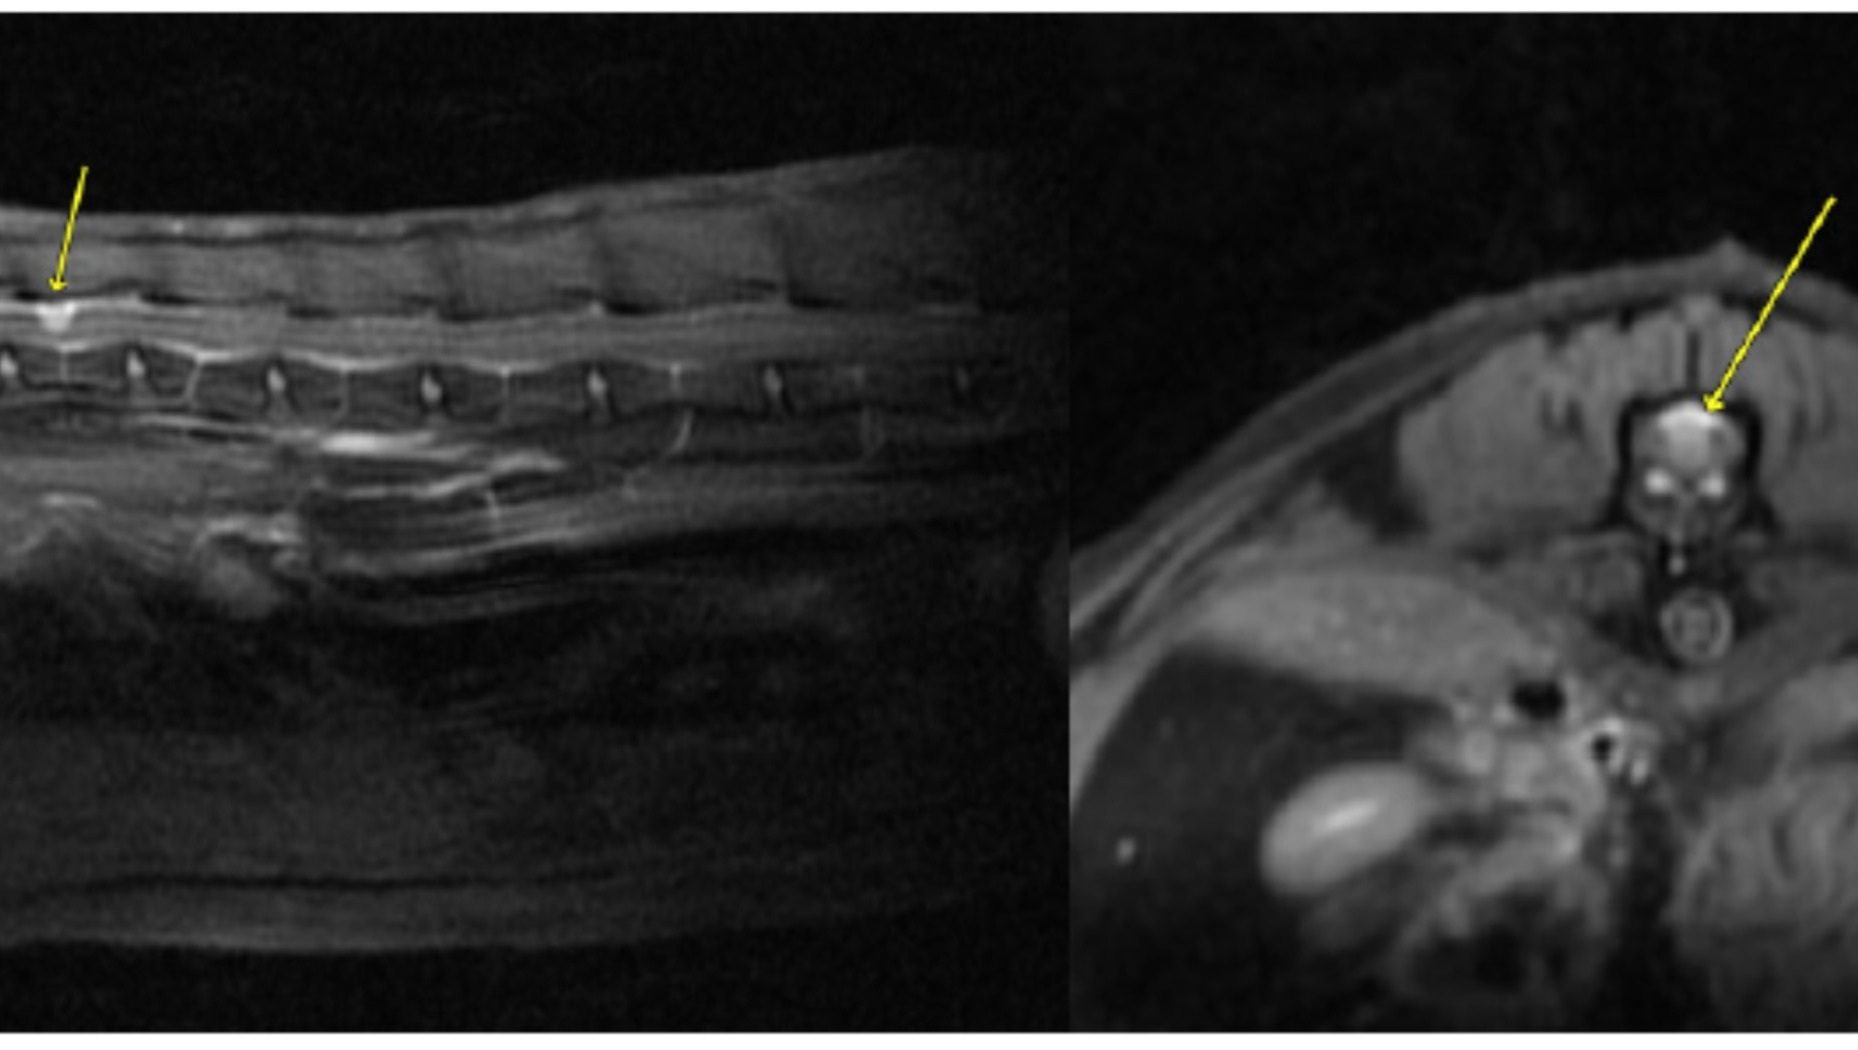

In late May of 2025 our cat, Badger, started walking oddly, acting like it was hard for him to coordinate his rear legs. After a few trips to our local vet to rule out the likely causes (nothing on xrays, blood work and kidneys were fine), we opted to take him to a Veterinary Teaching Hospital 3 hours away to see a neurologist. They suggested a MRI for further diagnosis. This procedure showed a small isolated mass on his spinal cord. Their team initially diagnosed it as a meningioma (non-cancerous tumor). To fully determine what it was the next option was surgery to remove the mass and get a biopsy. That went well (you can see the surgical incision in the main photo) however the surgeon said the mass was not on the cord, but in the cord, meaning it was much more likely to be cancerous. We braced for the worst, however based on the biopsy we learned that it was indeed a meningioma (although a very odd one). The image below of the MRI showing the location of the tumor on his 13th thoracic vertebrae.

Meningiomas are benign tumors that typically grow on the meninges (protective covering layers) of the brain or spinal cord. Meningiomas account for about 56% of neoplasms (tumors) of the Central Nervous System (CNS) in cats, however only 14% of those have been reported on the spine. Thus, we are dealing with a very rare type of tumor, one for which we have little scientific data. There are probably less than a handful or reported cases, and most of the case studies are for cats with brain meningiomas. The good news is that these tumors are not known to spread, and if removed can allow the cat to fully recover and live a long life.